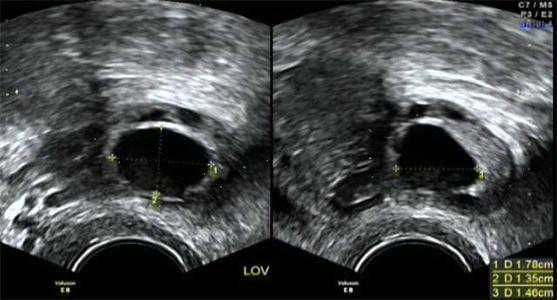

我们常用的方式是卵泡监测,这是一种很准确的方法。

通过B超可以直接看到卵泡的大小,监测排卵不仅能用来找排卵日,也能用来发现生殖系统的异样,提早发现,提早治疗。